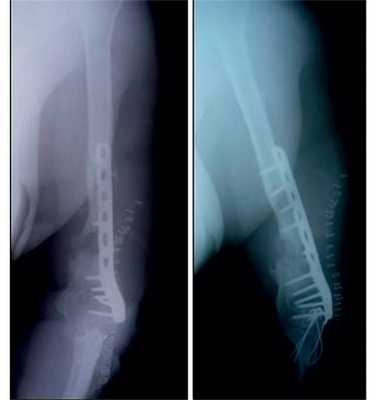

Больная П., 25 лет, поступила в стационар с жалобами на боли в левом локтевом суставе через 2 ч после травмы в результате падения на улице. При осмотре отмечены отек левого локтевого сустава, болезненность при пальпации, невозможность движений в суставе из-за боли. После клинико-рентгенологического обследования установлен диагноз: закрытый внутрисуставной оскольчатый чрезмежмыщелковый перелом левой плечевой кости со смещением отломков тип 13-С2 (рис. 2). Рисунок 2. Рентгенограммы больной П. с внутрисуставным оскольчатым чрезмежмыщелковым переломом левой плечевой кости со смещением отломков тип 13-С2.

Сосудистых и неврологических расстройств в дистальных отделах левой верхней конечности выявлено не было. При поступлении произведена анестезия места перелома, внешняя иммобилизация гипсовой лонгетной повязкой.

На следующий день под новокаиновым блоком плечевого сплетения произведена операция: закрытая репозиция и чрескостный остеосинтез левой плечевой кости спице-стержневым аппаратом внешней фиксации конструкции А.И. Городниченко. Через разрезы кожи и мягких тканей по наружной поверхности левого плеча длиной до 5 мм введено 2 кортикальных стержня в диафиз плечевой кости, один кортикальный и один спонгиозный стержень и 2 спицы с упорной площадкой в мыщелки и надмыщелки плечевой кости. После фиксации проксимальных стержней в аппарате под контролем электронно-оптического преобразователя произведена закрытая репозиция с помощью съемных рукояток с последующей стабилизацией дистальных стержней и спиц (рис. 3). Рисунок 3. Рентгенограммы больной П. после остеосинтеза левой плечевой кости спице-стержневым аппаратом. Кожа вокруг стержней ушита одиночными швами. Кровопотеря в ходе операции 20 мл. Продолжительность операции 40 мин.